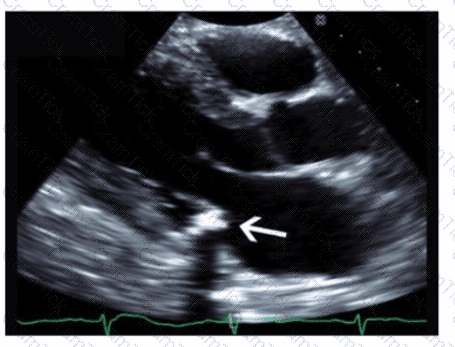

Which left ventricular regional wall segment is indicated by the arrow on this image?

Which condition is most plausible based on the finding indicated by the arrow on this image?